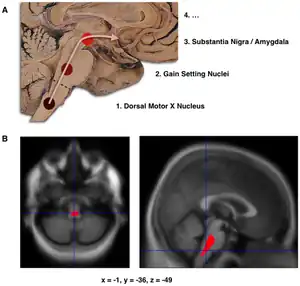

- Schematic initial progression of Lewy body deposits in the first stages of Parkinson's disease, as proposed by Braak and colleagues

- Localization of the area of significant brain volume reduction in initial PD compared with a group of participants without the disease in a neuroimaging study, which concluded that brainstem damage may be the first identifiable stage of PD neuropathology[63]